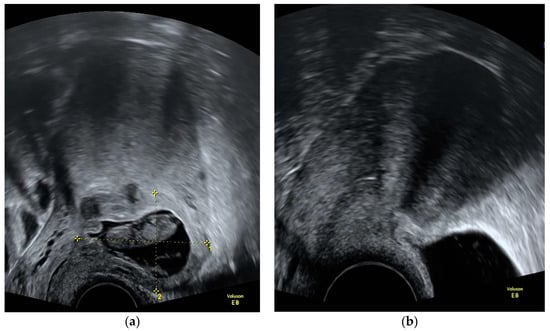

Prior to the MTX applications, serum laboratory results, including a blood count, electrolytes, urea, creatinine, and ß-hCG were obtained. Blood counts and serum ß-hCG were repeated a median of 4 days after MTX injection. It was decided depending on the ß-hCG decrease whether to repeat IM MTX after one week. If the ß-hCG decrease was adequate and no additional MTX was scheduled, primary care providers could take over further laboratory check-ups for patients who had a long commute to our institution. An example of a CSP at diagnosis before and after treatment with IC/IM MTX is provided in Figure 1.

Figure 1. Ultrasound image of a cesarean scar pregnancy before and after treatment with intrachorial and intramuscular methotrexate: (a) at initial diagnosis (11 + 1 gestational weeks); (b) 4 months after treatment with methotrexate.